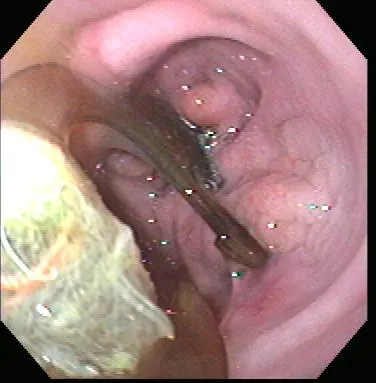

Gastroenteroscopy revealed a hard plastic foreign body (Figure 2) with curved, pointed ends. Points of the object were embedded in the gastric antral mucosa, resulting in hyperplasia. One of the curved points extended through the pylorus and hooked into the proximal duodenum (Figure 3). The endoscope could be passed around the foreign body into the duodenum, allowing biopsy of the duodenal mucosa. The gross appearance of the duodenal mucosa was normal (Figure 4). Attempts to remove the foreign body endoscopically were unsuccessful. Before the dog was sent to surgery for removal of the foreign body, colonoscopy was performed. The colon appeared normal on gross inspection (Figure 5). Biopsies were obtained from the cecum; ascending colon; transverse colon; and proximal, middle, and distal descending colon. At surgery, a gastrotomy incision was made in the pyloric antrum and the foreign body was forcefully removed. It was a plastic object used to secure the legs of a turkey carcass.

Endoscopy of the gastric antrum showing the foreign body and the mucosal proliferation induced by its presence